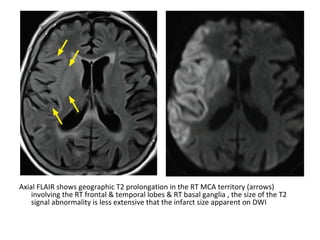

Axial FLAIR shows geographic T2 prolongation in the RT MCA territory (arrows)

involving the RT frontal & temporal lobes & RT basal ganglia , the size of the T2

signal abnormality is less extensive that the infarct size apparent on DWI